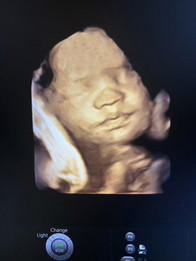

น้องพริม อีก1 เดือนนิดๆจะได้เจอกันแล้วนะลูก❤️❤️❤️ พ่อ แม่ รักหนูมากๆนะคะ